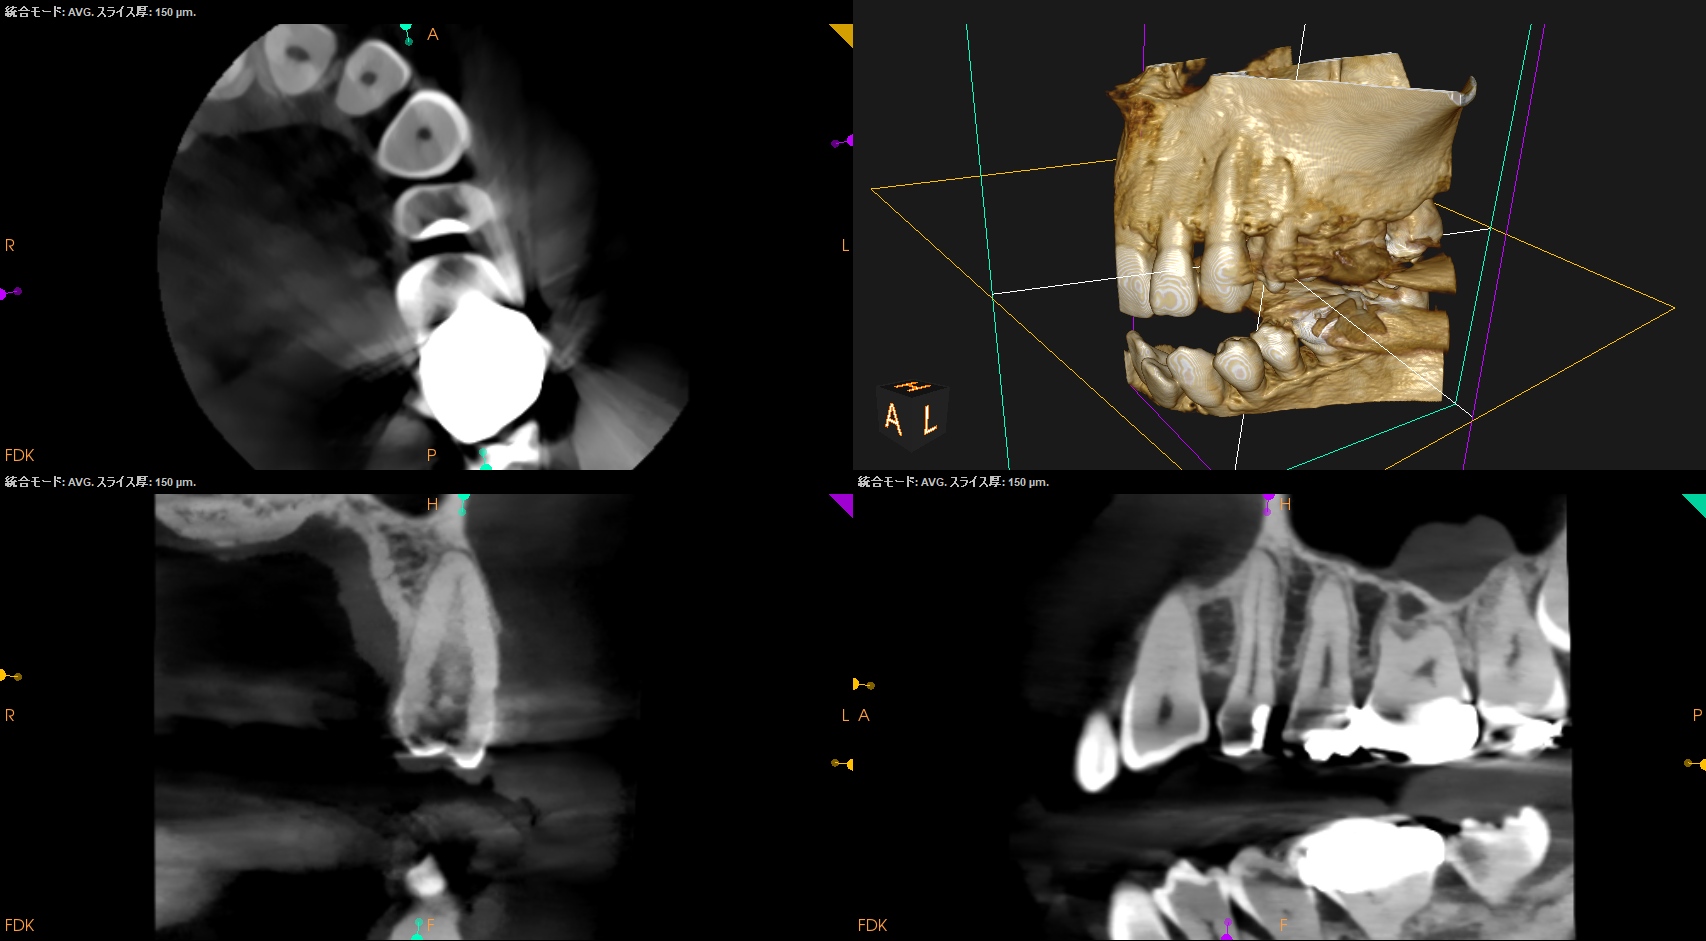

#12 RCT(2024.3.7)

では、再根管治療か?といえば、初期治療で穿通できなかったのである。

ということは、治療方法はApicoectomy一択だ。

その際は、

それほど難しいApicoectomyではない、とわかる。

CBCTを分析すれば、だ。